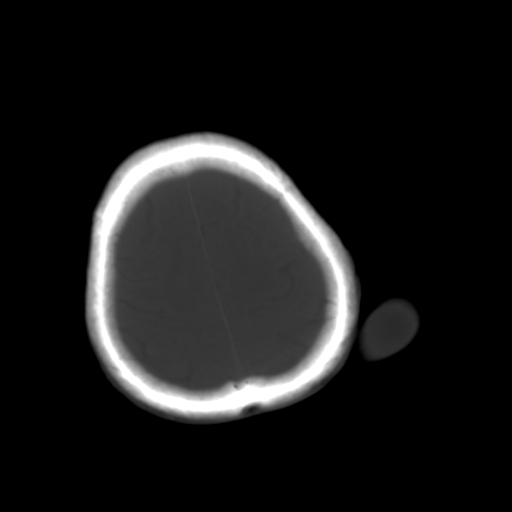

标题: CT25147:男,62岁,右侧肢体活动障碍不灵活三天。 [打印本页]

男,62岁,右侧肢体活动障碍不灵活三天,左侧头皮肿物十余年(ct值8hu)。

多发腔梗!皮下脂肪瘤!

1)多发性腔隙性脑梗塞。2)脑白质病。3)脑萎缩。4)左侧枕顶部头皮下皮样囊肿,不排除脂肪瘤。

1)多发性腔隙性脑梗塞。2)脑白质病。3)脑萎缩。4)左侧枕顶部头皮下皮样囊肿或表皮样囊肿。